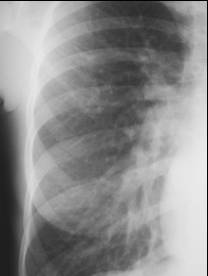

Normal